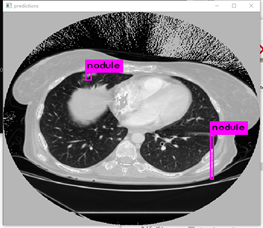

训练了大概3天,迭代了48000次,loss值约0.03(GTX1080)。

原图:

预测:

在应用yolov3算法进行肺结节检测时,发现其在实际应用中仍存在一定局限性。具体表现为:1)迭代训练不足导致模型尚未达到充分收敛的状态;2)有必要对训练数据集进行聚类分析以优化参数设置,并调整anchor框大小与比例参数设置以进一步提升检测精度。

下图左边是预测,右边是根据标注生成的ground truth。